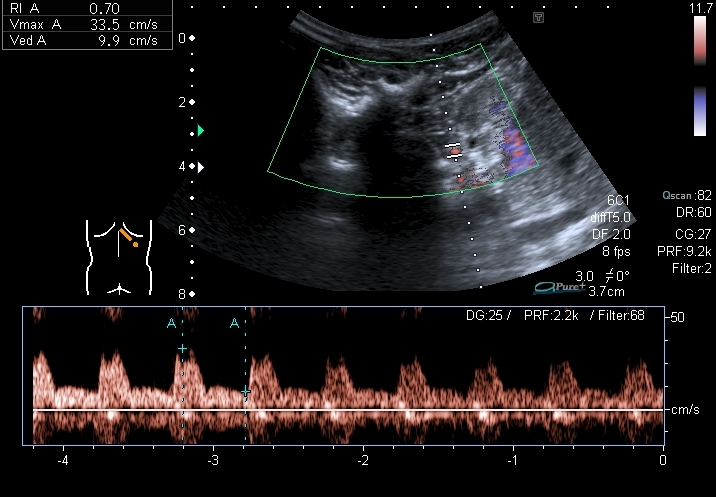

Спектрограммы кровотока в правой и левой почках:

I20121224144609218.jpg

I20121224144609296.jpg

По клипам я бы предположил запущенную двухстороннюю рефлюкс-нефропатию + тумор левой почки.

"Маленькие белые почки" с расширением ЧЛС и мочеточников, умеренной латерализацией устьев, без видимых на высокочастотном УЗИ кист. Печень без видимых на высокочастотном УЗИ кист. Опухоль слева.

МЦУГ, перевод в Минск (нефректомия слева + трансплантация почки).